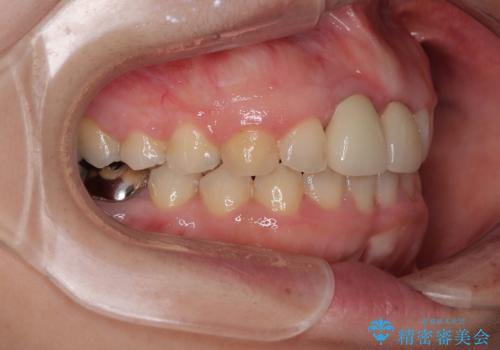

前歯のクラウンは変色が顕著なため、矯正治療後にオールセラミッククラウンによる補綴治療を行うこととしました。

前歯のクラウンは、歯肉内深くに削り込まれており、歯肉の炎症が継続していたため、矯正治療後に歯周外科処置を行い、歯肉の腫れを改善させました。